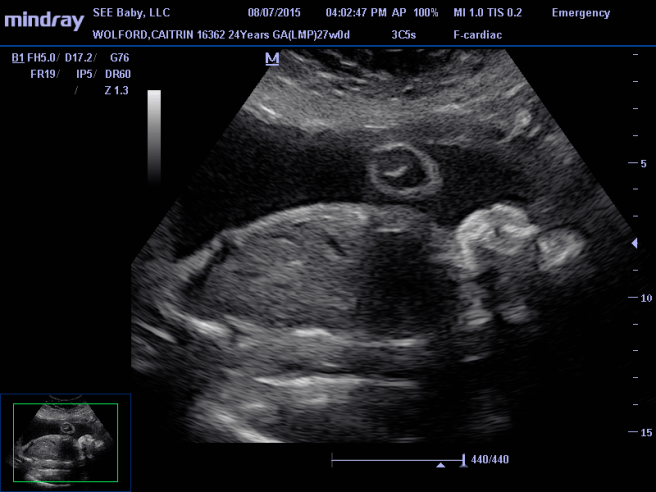

11896223_909770195751108_5671680245353682992_n

This is Brielle’s heart. The dark part in the middle of the blob is her heart.